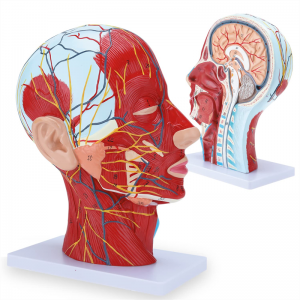

【1:1 Lifesize】Median Section of 1:1 natural large head & neck superficial neural vascular muscle model (right side). Fine workmanship. Offering a full range of anatomical features.

【Superficial Neurovascular Muscle Model】Highly detailed, numbers marked, detachable ear, deepen the understanding of the superficial muscles, vessels, nerves and the internal structures of the head & neck. Red-artery, blue-vein, yellow-nerve.

【Features】It shows the superficial muscles of the exposed face; the superficial blood vessels & nerves of the face & scalp; the inner structures of parotid gland & upper respiratory tract; the sagittal cross-section structure of the cervical spine.

This model is a natural large head and neck superficial neurovascular muscle model, 1 component, showing the details of the human right head and neck and median sagittal section, including the exposed superficial muscles of the face, superficial vessels of the face and scalp, nerves and the medial structure of the parotid gland and upper respiratory tract, and the sagittal section structure of the cervical spine